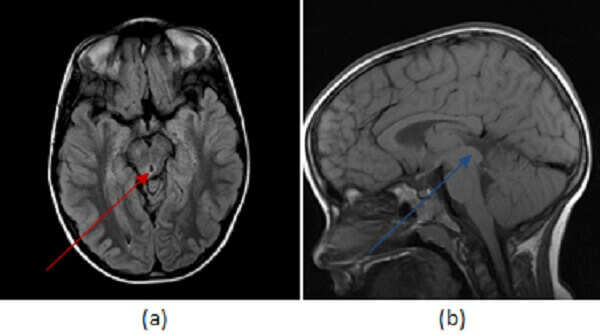

Figure 1: (a,red arrow) FLAIR hyperintense signal expands the right tectal plate with T1 isointense fullness in the same location (b,blue arrow) that does not enchance (c, green arrow).

Tectal plate gliomas are aggressive, infiltrating malignancies of the tectum (the dorsal midbrain). They are generally expansile T2/FLAIR hyperintense minimally enhancing lesions that expand the tectum and compress the midbrain leading to hydrocephalus. They most commonly present as WHO grade 3 (anaplastic astrocytoma) tumors, but may undergo secondary transformation into a glioblastoma multiforme (GBM). Treatment involves resection with adjuvant chemo and radiation therapy but prognosis is poor, with a median survival of 2-3 years.